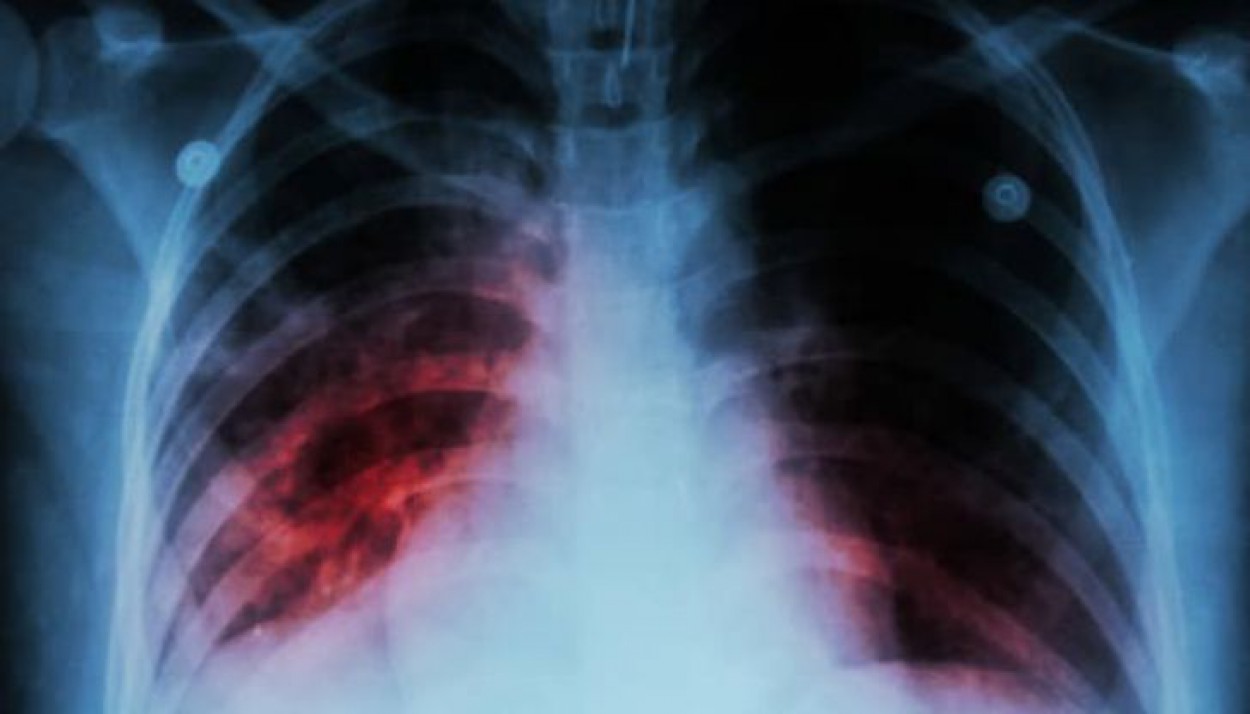

ULAC medikai primena, kad TB infekcijos šaltinis yra atvira plaučių TB sergantys ligoniai, pastarieji kosėdami, čiaudėdami ir skrepliuodami į aplinką išskiria gausų kiekį ligos sukėlėjų – tuberkuliozės mikobakterijų. Ši liga ypač grėsminga naujagimiams, kūdikiams ir vaikams iki 5 metų.